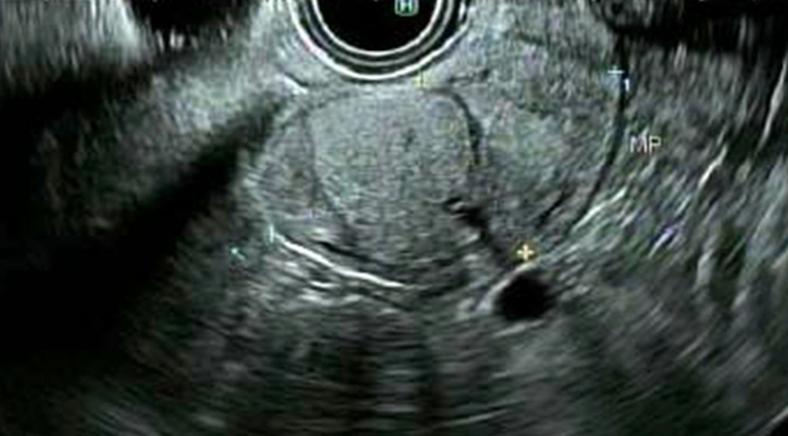

Endoscopic resection of a duodenal Brunner gland hamartoma presenting with GI bleeding.

https://cdn.ncbi.nlm.nih.gov/pmc/blobs/1de3/7570429/1c01dc3b363f/gr1.jpg